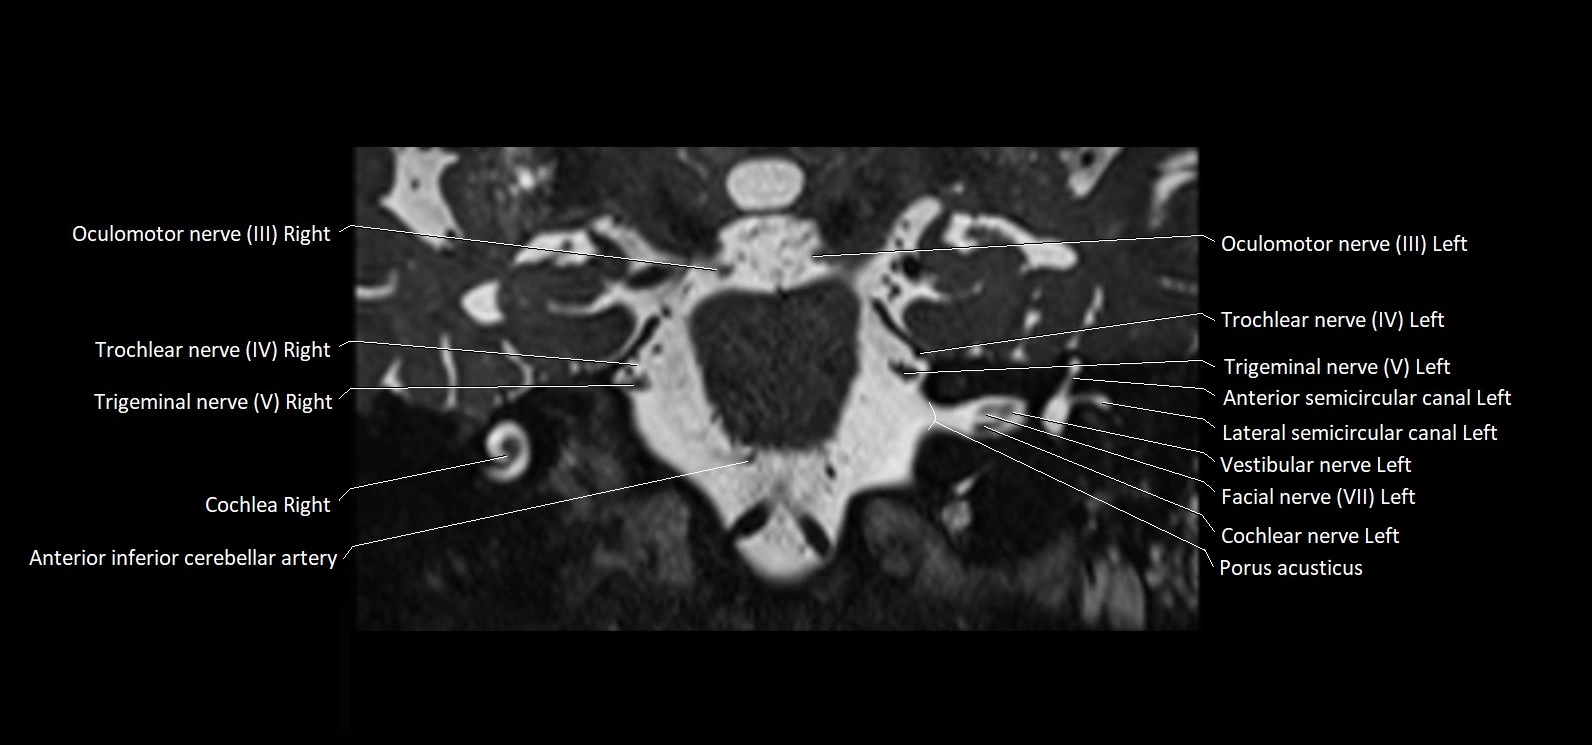

MRI Appearance

• The abducens nerve is a small, thin, linear structure

• Best visualized on high-resolution T2-weighted 3D MRI sequences (e.g., FIESTA or CISS)

• Seen as a hypointense (dark) line running from the brainstem at the pontomedullary junction, traversing the prepontine cistern, and entering Dorello’s canal under the petrosphenoidal ligament, then into the cavernous sinus, and finally the orbit

• May be challenging to visualize in standard MRI due to its small size

• Pathology may be inferred by absence, displacement, or enhancement of the nerve